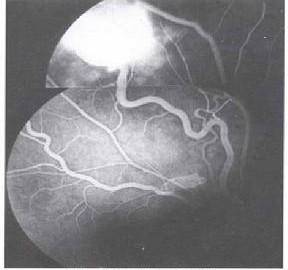

3.血管网状细胞瘤

血管网状细胞瘤又称血管母细胞瘤,是由脑神经和脊髓神经所产生的一种高度血管分化的良性肿瘤,剧烈疼痛是它的唯一症状,病因及发病机制极其复杂,并且具有家族遗传性。它是良性肿瘤,早诊早治效果好,手术彻底切除可根治。